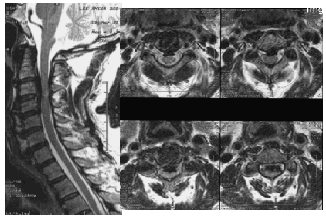

MRI: 척수와 신경의 압박 정도 및 연조직 상태를 평가하여 손상 정도를 진단하는 데 유용합니다.